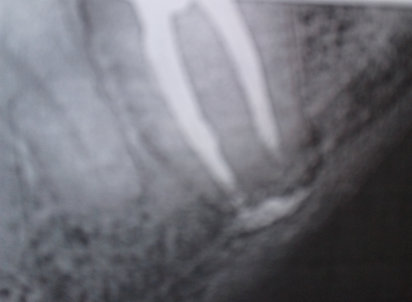

Месяц назад мне начали лечить очень воспаленный зуб, седьмой нижний слева. После пломбировки каналов наложили временную пломбу. После наркоза зуб болел при накусывании 2 недели, потом боль начала стихать и на сегодняшний день зуб не болит. При постукивании по зубу, я обратил внимание, что боль идет со стороны щеки. Сделав снимок увидел, что канал слева не запломбирован до конца. Врачи говорят, что все в порядке. Я начал интересоваться этим вопросом по причине боязни потерять этот зуб, на который будет крепиться мостовидный протез.

Если по истечении 6 месяцев проведен рентген контроль, и не выявлено воспаления корня, то навряд ли оно там появится.